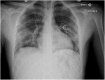

Coronavirus 2 (SARS-CoV-2) is now considered a pandemic causing Coronavirus disease (COVID-19), multiple fatalities and morbidities which have been associated with it worldwide. We report a severe pneumonia causing acute respiratory distress syndrome due to a coinfection with SARS-COV-2 and Parainfluenza 4 virus in a Hispanic 21 year old male in Florida, USA. The case represents the importance of prompt diagnosis and awareness of the potential co-infection with other respiratory viruses and this novel deadly virus.